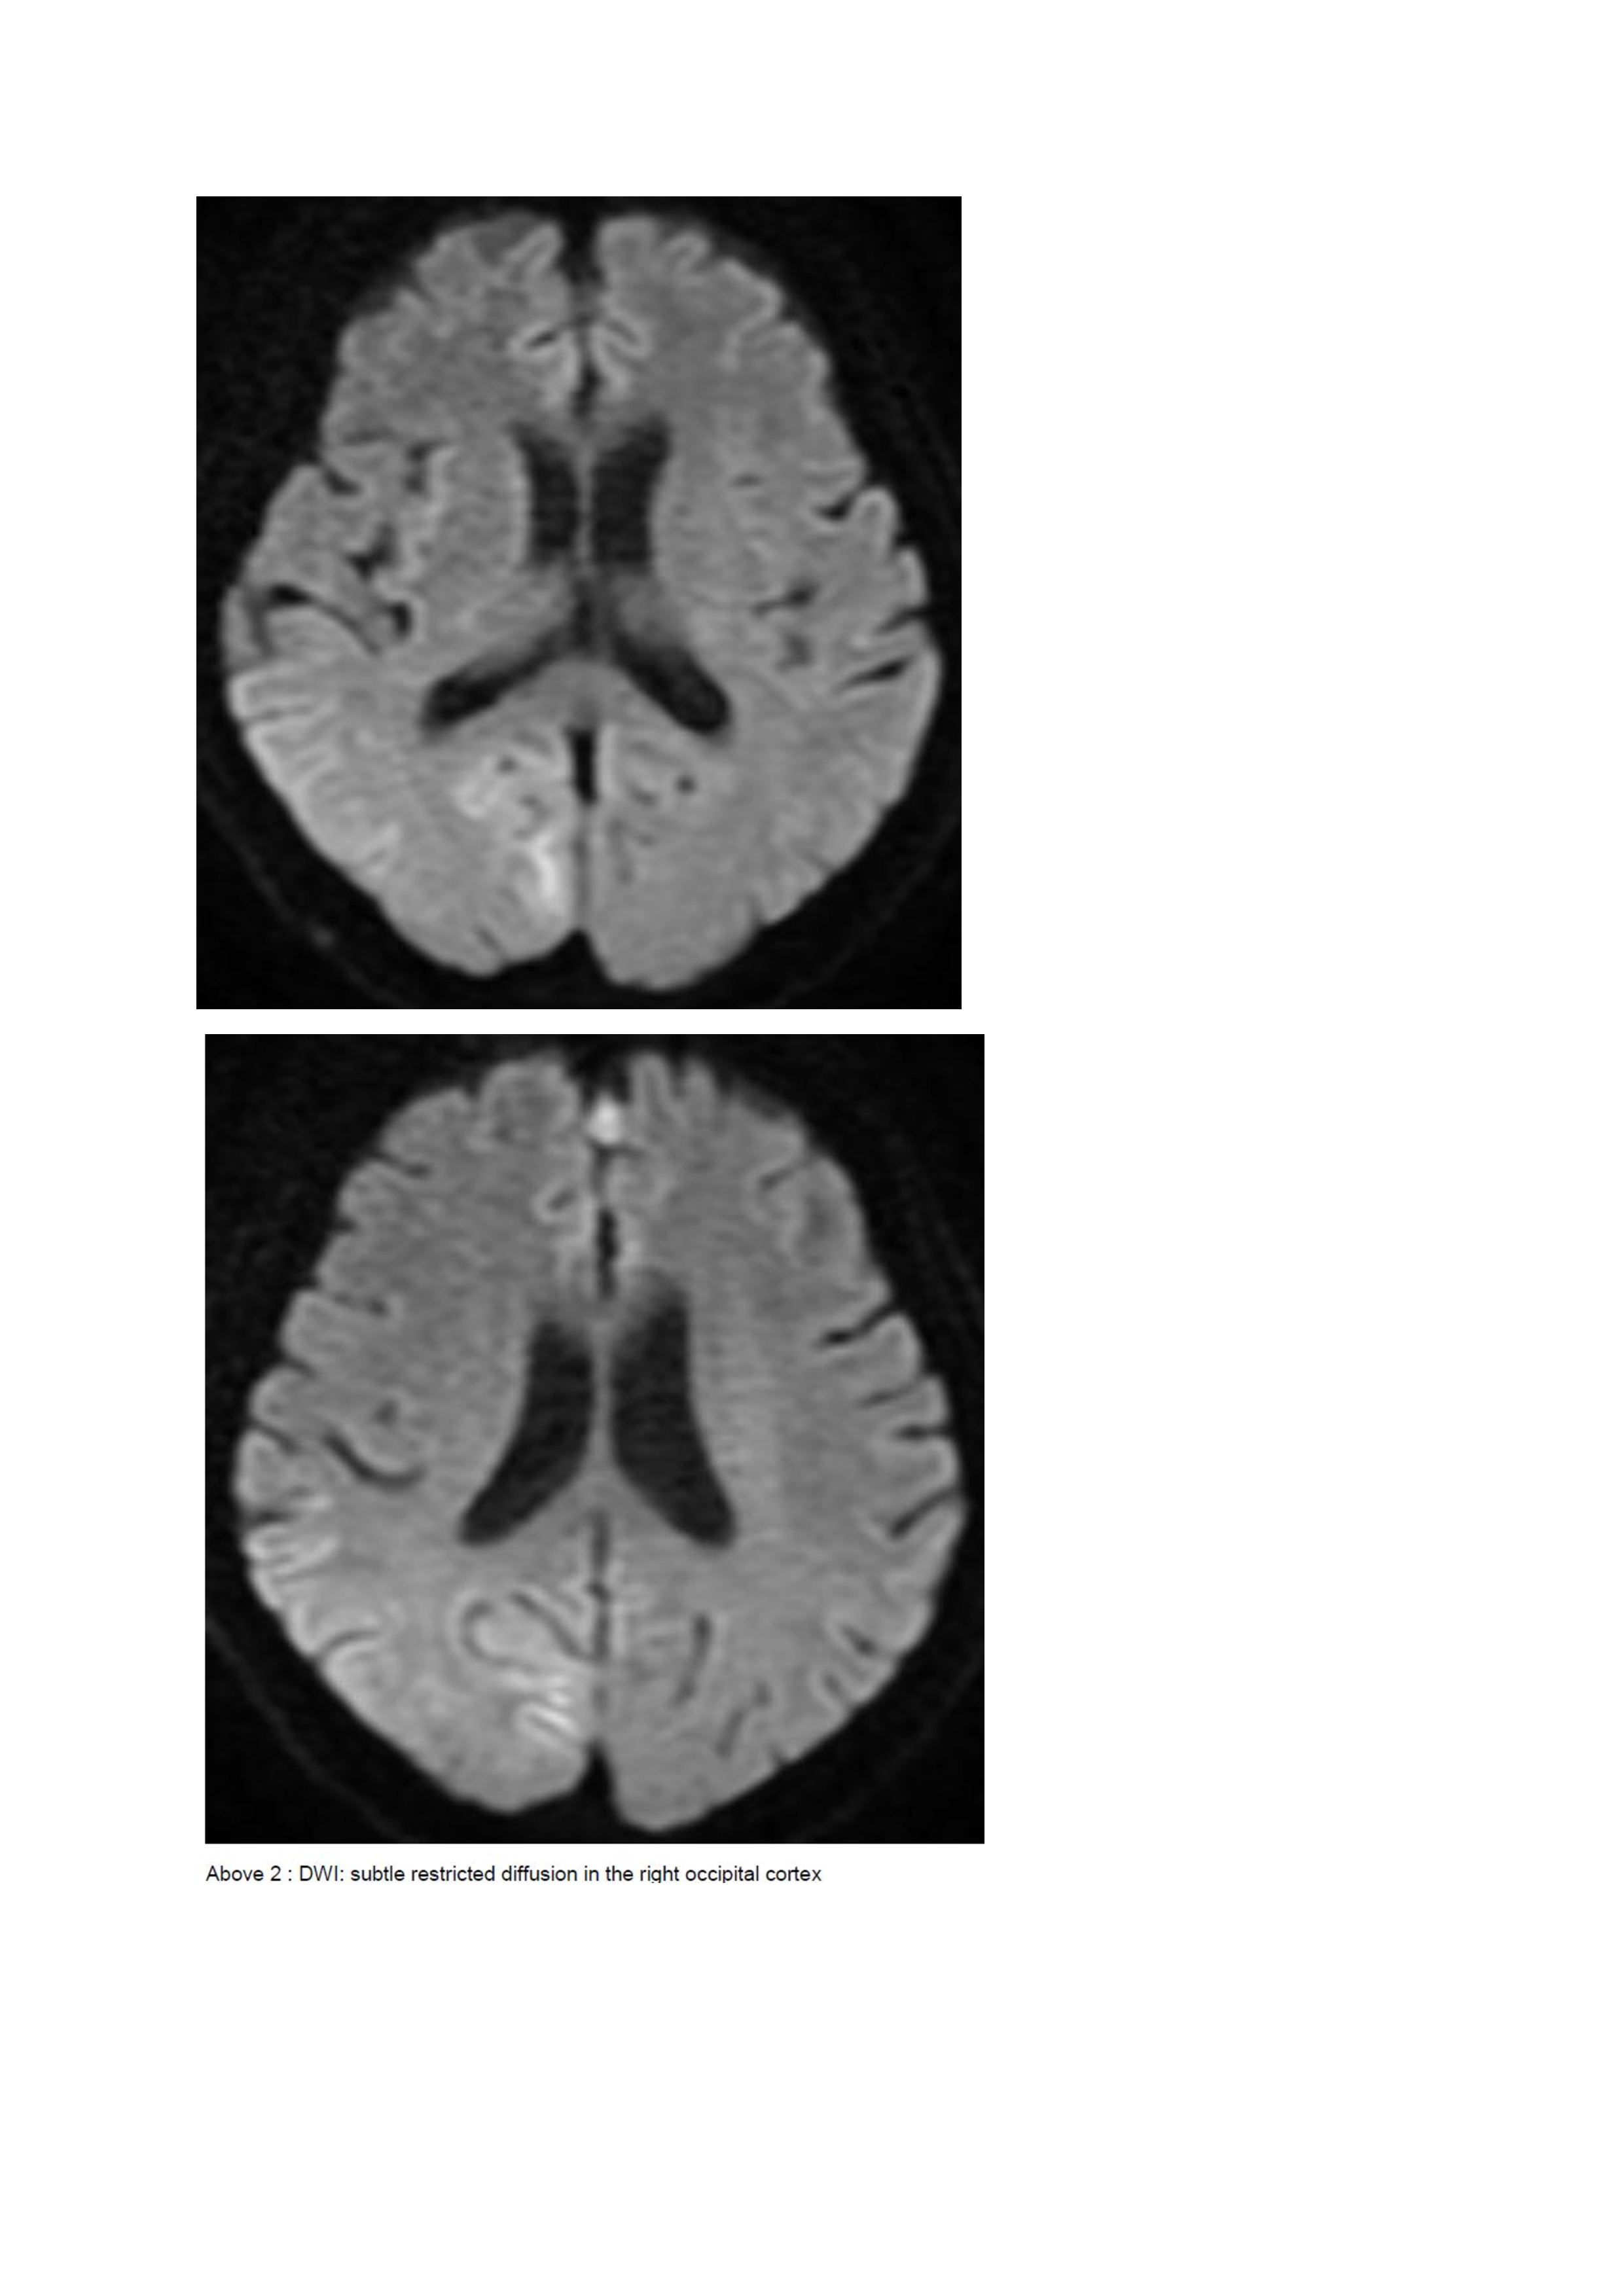

Results:

A 67-year old woman with chronic hypertension, hyperlipidemia and diabetes mellitus non-compliant to medication presented with a 10-day history of recurrent visual phenomena in the left visual field. She described stationery multi-coloured flashing lights which decreased in intensity, brightness and size after 3 minutes. She was alert and conscious during attacks. There was no limb jerking. Neurological examination was normal with no visual field defect. Capillary glucose was 28.1 mmol/L, Hba1c 9% and B-hydroxybutyrate < 0.1. She was treated with actrapid 8 units, glipizide 5 mg BD and empagliflozin 12.5 mg OM. Interictal electroencephalogram was normal with no epileptiform activity. Brain magnetic resonance imaging revealed restricted diffusion in the right occipital cortex with corresponding cortical thickening and increased FLAIR signal with subtle hypodensity on GRE sequence. Her visual symptoms improved dramatically with hydration and diabetic control. She was treated with a short course of keppra. One month later repeat MRI brain showed resolution of the DWI and FLAIR abnormalities.

Initial dwi